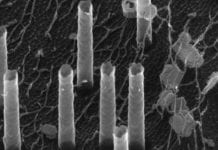

Using microneedles for painless drug delivery

Researchers have suggested using microneedles for immunotherapy to vaccinate or treat diseases such as cancer and autoimmune disorders, with minimal pain, invasiveness, and side...